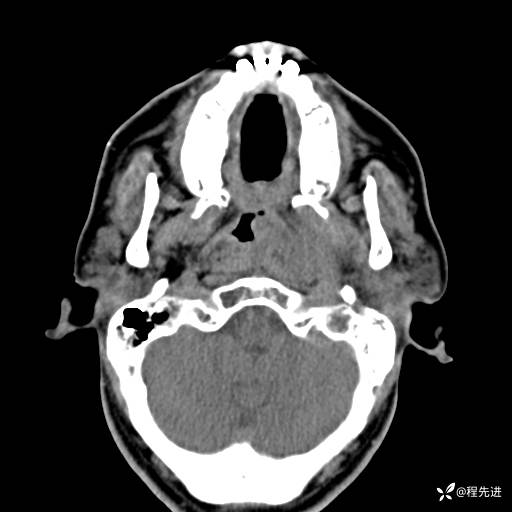

CT平扫: